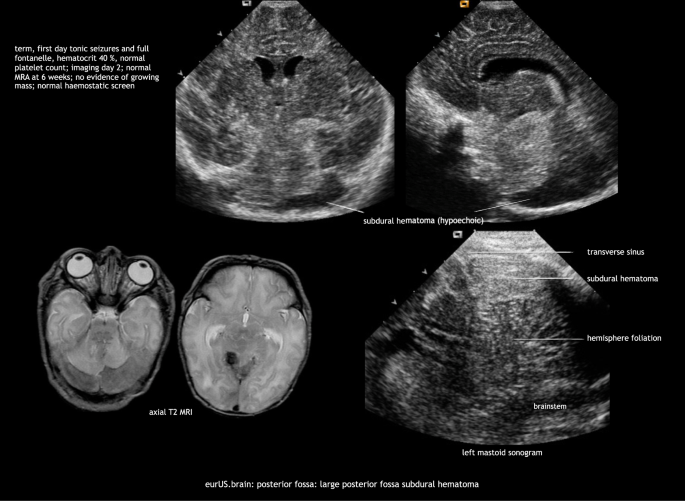

Minor subdural hemorrhages are commonly detected by MRI in asymptomatic term infants after vaginal delivery, usually they are undetectable by CUS.44 Major subdural hemorrhage in the newborn can occur above and below the tentorium and is often the result of traumatic delivery. Major infratentorial hemorrhage occurs after tentorial laceration—with rupture of the straight sinus, vein of Galen, transverse sinus, or infratentorial veins—and after occipital osteodiastasis with rupture of the occipital or other sinus. Affected infants usually develop neurologic symptoms related to brainstem or cranial nerve compression. Early recognition is crucial because deterioration can be rapid and prompt surgical intervention can be lifesaving. In general, computed tomography (CT) or MRI are considered superior to CUS to demonstrate the extent of the lesions. However, there are clear ultrasound features of major posterior fossa hemorrhage both on AF and MF views. Recognition of these features facilitates early diagnosis and timely intervention. Features of major posterior fossa hemorrhage on AF views are: unexplained ventricular dilatation; apparent broadening of the “tentorium”; difficulty to delineate midline posterior fossa structures (cerebellar vermis, pons) or an area of increased echogenicity above the vermis in midsagittal plane. Features on MF views are: mass effect on cerebellum with shift of one or both hemispheres, compression of the fourth ventricle; extra-axial blood surrounding cerebellar hemisphere(s) and/or between hemisphere and tentorium (of note: acute hemorrhage often has an echolucent appearance); thickening of the perimesencephalic cisterns indicating subarachnoid bleeding (Fig. 7).